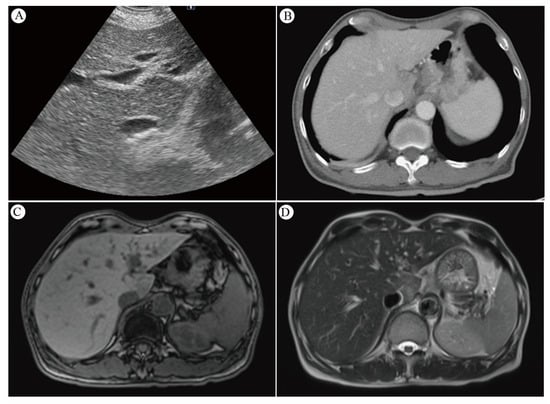

| Rabe et al. (2016) [12] | 53 | uT3N M1 0-squamous | 5 cycli (carboplatin + paclitaxel) | 50.4 Gy-3D conformal | 2w | Nodular | Well-defined, low attenuation | Hyperintens T2-weighted | Perop | AP ↑ | 12 months |

| Demey et al. (2017) [46] | 42 | uT2N M1 0-adeno | Concurrent Oxaliplatin + 5-FU | 45 Gy-3D conformal | 4w | Nodular | Patchy-defined, low attenuation in segment 2 | Hyperintens T2-weighted | Perop | Normal | 18 months |